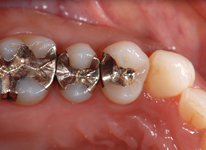

セラミックインレー

昔詰めた銀歯のお色が気になる方や金属アレルギーが心配な方へ

透明で美しく変色しにくい素材をおすすめします。見た目が天然歯に近い素材なので、区別がつきにくく年数がたっても変色しにくいことが特徴です。

Before

After